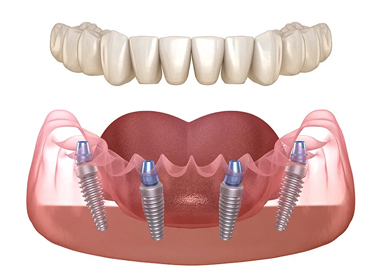

Implant Retained Dentures

All-On-4/Permanent Implant Bridge